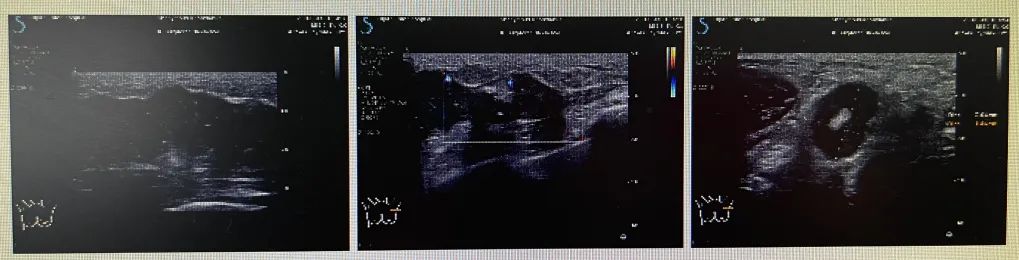

左侧腺体外上象限见一低回声团块,大约5.1cm×1.7cm×4.4cm,界欠清,形态不规则,边缘见毛刺及蟹足状改变,周边见高回声晕,内见强回声点,局部可见较丰富血流信号。左侧腋窝见数个淋巴结,大者约2.0cm×1.8cm,界清,可见淋巴门部结构,实质弥漫性增厚,可见较丰富血流信号。左侧锁骨下见数个淋巴结,大者约0.8cm×0.5cm,界清,未见淋巴门部结构,可见少量血流信号。

2021.8-2022.1开始给予EC-THP方案化疗(EC×4序贯THP×2+TH×2)患者由于经济原因,后续要求停用帕妥珠单抗,采用单靶治疗,彩超疗效评估(如下表格)

2022.1月新辅助治疗结束后评估彩超